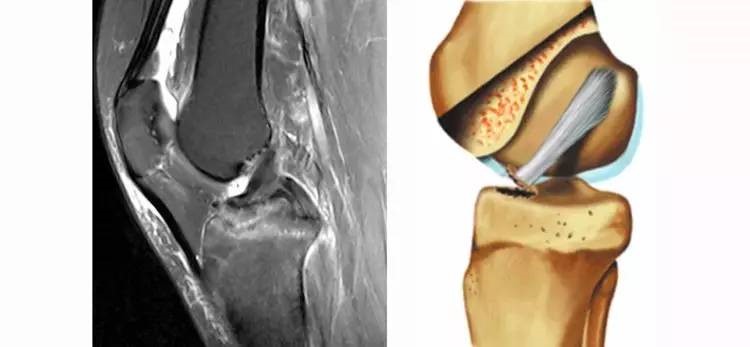

11.半月板桶柄状撕裂:为膝关节的一种严重损伤,常伴有ACL损伤。

24.jpg